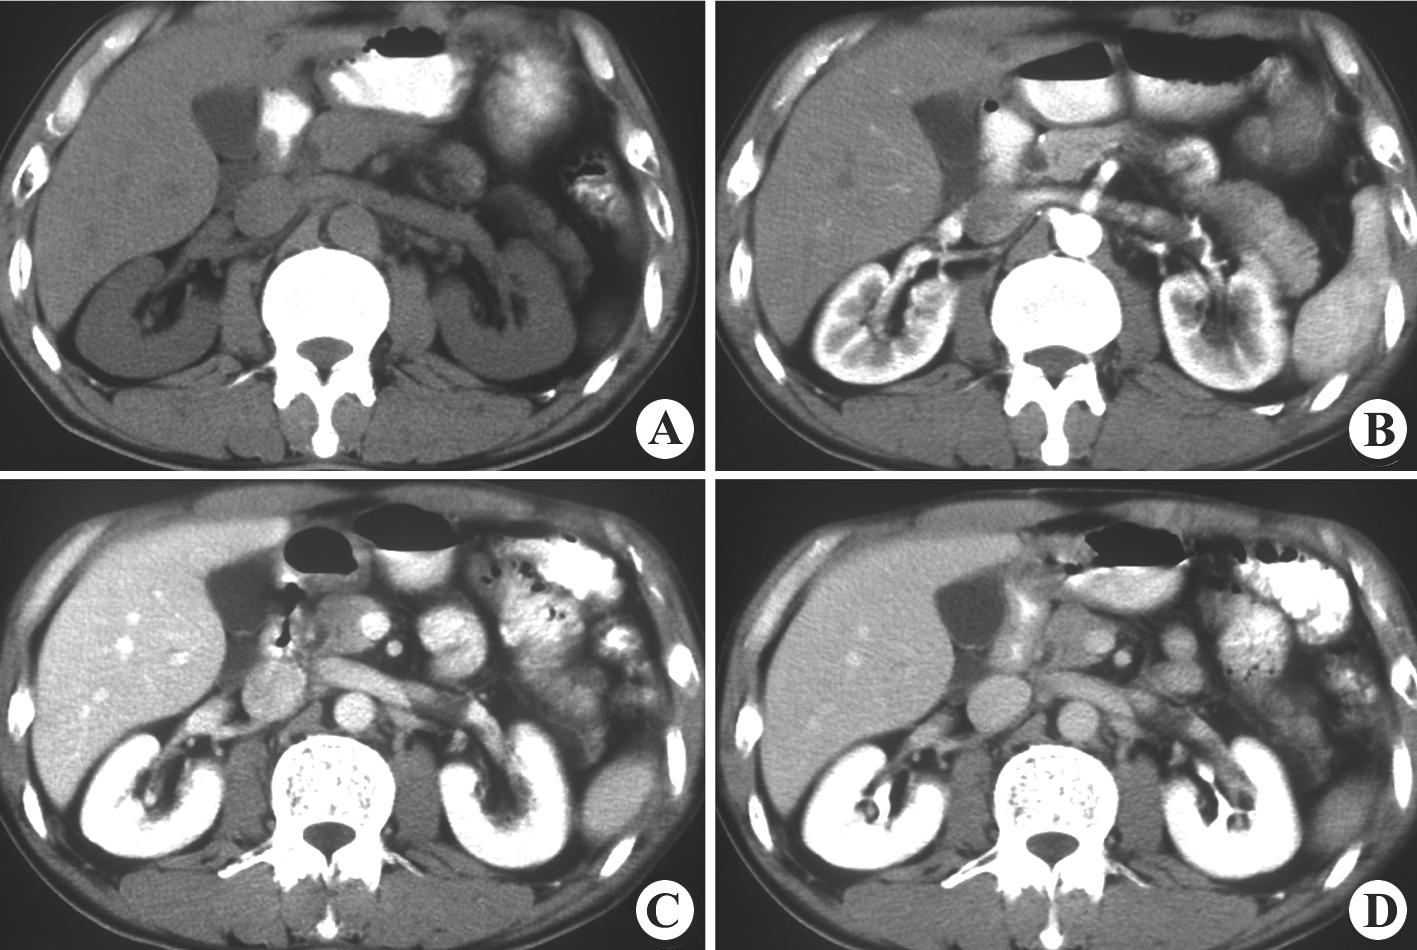

泌尿系统1 - 知乎

图片尺寸1417x950